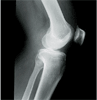

62 years old lady with severe varus both knees and osteoarthritis

Pre

Op

Pre Operation Xrays of limb